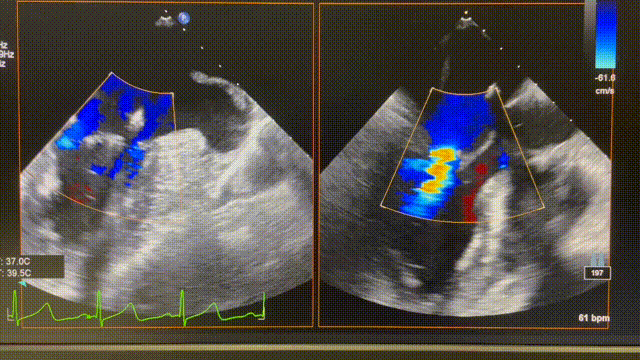

患者为74岁女性。术前心超显示后叶P2脱垂,伴极重度二尖瓣反流(VCW 9mm*16mm),图2。患者全麻后,在超声和射线引导下器械经股静脉穿刺房间隔,通过输送系统送入患者左心房,到达二尖瓣膜反流处,在经食道超声及DSA引导下,术者通过反复评估二尖瓣膜脱垂范围、抓捕位置、反流程度,精准夹合,成功植入1枚ValveClasp瓣膜夹。术后即刻左房压力及V波减低,患者反流从5+减少到1+(图3),跨二尖瓣平均压差3mmHg,肺静脉逆流消失,血流动力学改善明显,手术取得圆满成功。

图3 术后心超图。